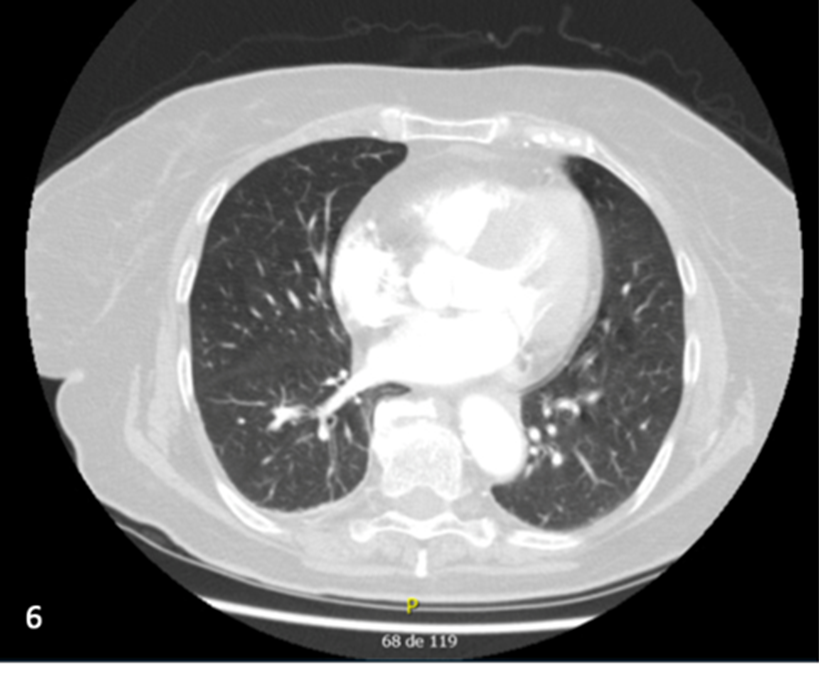

Primary Small Cell Neuroendocrine Carcinoma of the Mediastinum: Case Report of a Rare Entity

Magno Giovani Zanellato, Elida Paula Benquique Ojopi, Daniela Cristina dos Santos Souza

bjcr79